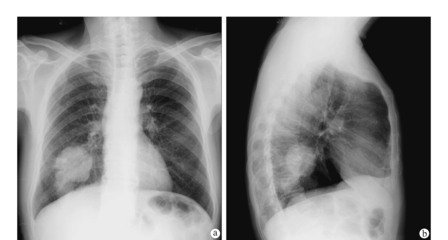

肺大疱一般继发于小支气管的炎性病变,如肺炎、肺结核或肺气肿。临床上常与肺气肿并存。因小支气管发生眼性病变后引起水中、狭窄,造成管腔部分阻塞,产生活门作用,使空气能进入肺泡而不易排除,致使肺泡内压力升高。炎症使肺组织损坏,肺泡间隔逐渐因泡内压力升高而破裂,肺泡互相融合形成大的含气囊腔。如果肺泡破裂后空气进入脏胸膜下间隙,则形成胸膜下大疱。肺大疱有单发也有多发。继发于肺炎或肺结核者常为单发或只有数个大疱,亦无明显肺气肿同时存在;继发于肺气肿者常为多发,表现为几个大疱伴有多个小疱,大疱周围的肺实质常伴有阻塞性肺部病变和肺气肿。肺大疱以位于肺尖部及肺上叶边缘多见。疱壁很薄,大小不一,数目不定。既可表现为宽基地座,亦可表现为狭颈体大的大疱。显微镜下可见疱壁为肺泡扁平上皮细胞,有时可仅有纤维膜或纤维结缔组织存在。

1.自发性气胸肺大疱可以没有任何症状。在突然用力,如剧烈咳嗽、提重物或体育运动时压力突然增加,肺大疱破裂,气体自肺内进入胸膜腔,形成自发性气胸时,可能出现呼吸困难,气急、心慌,脉搏加快等,气胸使胸膜腔负压消失,气体压缩肺组织使其向肺门部萎陷,萎陷的程度取决于进入胸腔的气体的多少,以及肺及胸膜原有病变的病理情况,进入胸腔的气体量大,肺组织原有病变轻,顺应性尚好的,肺萎陷较多,有时可达到一侧胸腔的90%,气体迅速进入胸腔,肺组织急速萎缩,则症状严重,甚至有发绀。如果患者除肺大疱以外,尚合并有肺气肿、肺纤维化、肺组织长期慢性感染等病变,肺大疱破裂时虽然有一部分气体进入胸腔,而肺组织萎陷程度可以较轻,但因为患者原有肺功能已减退,症状也较重。X线可见被压缩的肺形成的气胸线,如果有粘连存在,则气胸线不规则。肺大疱破裂后,其中一小部分裂口较小,肺组织萎缩后裂口自行闭合,漏气停止,胸腔积气逐渐吸收,胸腔负压恢复,肺复张痊愈。

2.张力性气胸若肺大疱破裂后形成活瓣,吸气时胸腔负压增高,气体进入胸腔,呼气时活瓣关闭,气体不能排出,尤其是咳嗽时,声门关闭气道压力增高,气体进入胸腔,声门开放后,气道压力减低,裂口又闭合,每一次呼吸和咳嗽都使胸腔内气体量增加,就形成张力性气胸。张力性气胸时患侧肺组织完全萎缩,纵隔被推向健侧,在健侧肺组织亦被压缩的同时心脏大血管移位,大静脉扭曲变形,影响血液回流,造成呼吸循环严重障碍,患者可出现呼吸困难、脉快、血压下降,甚至窒息、休克。患侧胸廓隆起,多伴有患侧皮下气肿,气管明显向健侧移位,病情危重,常需要急诊处理。

3.自发性血胸肺大疱引起的自发性血胸,多数由肺尖部的大疱或大疱周围的肺组织与胸顶粘连及粘连撕裂活动出血。粘连带中的小动脉直径可达0.2cm,血管起源于体循环,压力较高,同时胸腔内是负压,更增加了出血的倾向。另外,由于肺、心脏、膈肌运动的去纤维化作用,胸腔内的血液不凝固,因此出血很难自动停止。临床症状可因出血的快慢而不同,出血缓慢时,患者可表现为逐渐加重的胸闷,呼吸困难,X线可见膈角变钝,或胸腔积液的抛物线影像。出血迅速时,短期内可以有休克表现。